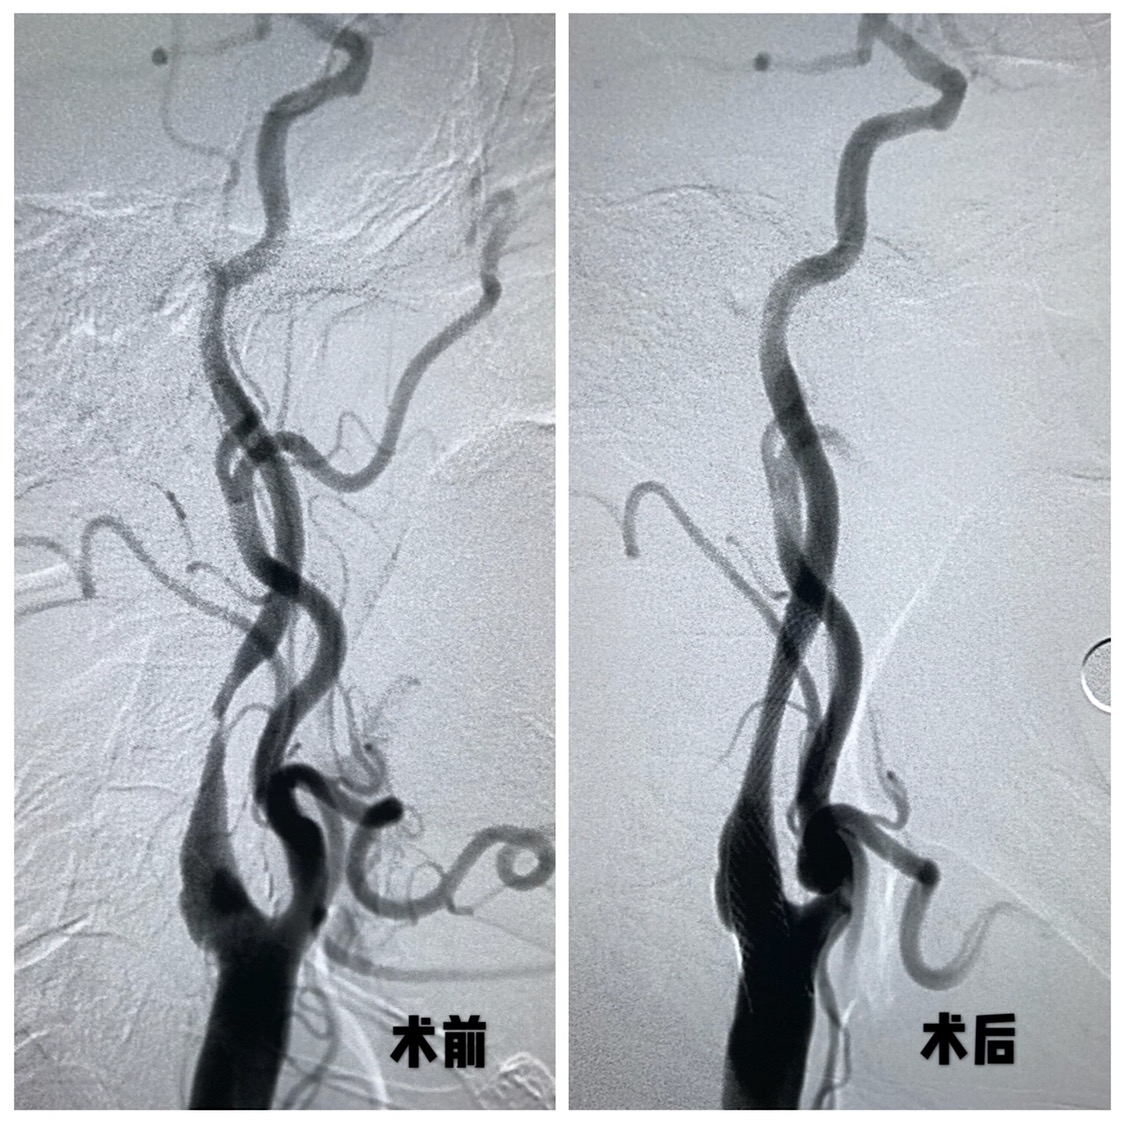

DSA:右侧颈内动脉窦部以远线性狭窄,窦部可见粥样硬化斑块,局部溃疡斑形成,动态可见造影剂滞留,颅内血管显影差。

远端保护伞保护下,4/30球囊预扩后狭窄改善

WALLSTENT 9/40支架定位准确后释放

支架释放后狭窄解除

支架完全覆盖斑块,狭窄解除,支架形态柔顺贴合血管,无明显残余狭窄

术后颅内血供明显改善,胚胎型大脑后动脉显影良好。